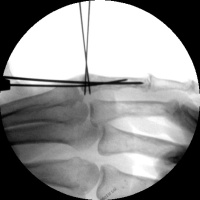

| Closed reduction and insertion of interfragmentary and proximal fracture fragment pins. |

| Pins were bent to

overlap and then bonded with heated thermoplastic

splint material. |